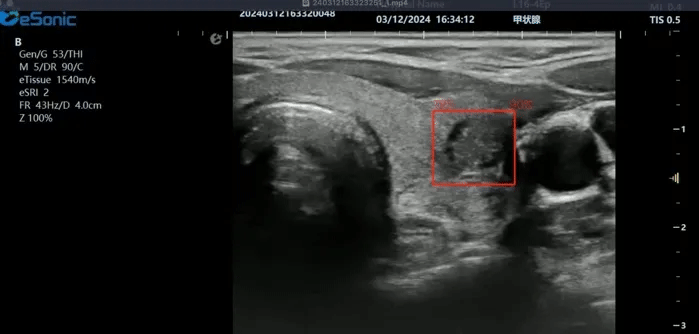

利来国国际网站医疗(ESI)表示,其最新的人工智能功能可以帮助到医疗机构的工作效率,功能包括,实时、动态、快速自动识别病灶,良恶性病灶概率预测,甲状腺结节和乳腺的二维灰阶动态自动实时检测需求,提供多个结节动态检测轮廓框。实时获取多幅具备临床特征(大小、属性等)的结节切面,同时提供当前切面所示结节的结节大小、属性特征、TI-RADS 分级。

对于甲状腺结节相关的自动检测功能,甲状腺结节病灶检出率≥95%,良恶性分类灵敏度≥90%、良恶性分类特异度≥85%。